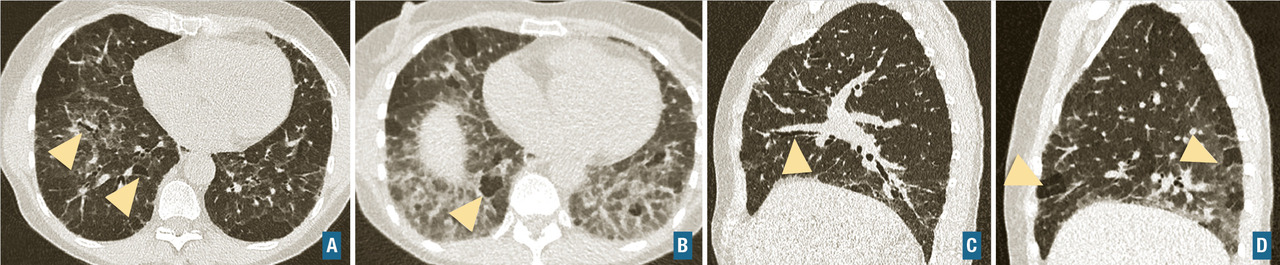

Les symptômes comprennent une dyspnée, une toux, des râles « piaulants » (squeaks) à l’auscultation et parfois des signes généraux semi-retardés : frissons, asthénie, fièvre. Le scanner thoracique met en évidence une atténuation en mosaïque à trois niveaux de densité, des plages de verre dépoli et des nodules flous centrés sur les bronches (fig. 5). Un piégeage aérien est fréquemment retrouvé, et se manifeste par une augmentation du contraste entre zones saines et pathologiques sur les coupes en expiration. Des signes de fibrose sont présents dans les formes fibrosantes. Une lymphocytose > 20-30 % dans le lavage broncho-alvéolaire conforte le diagnostic. L’histologie met en évidence une bronchiolite lymphocytaire, une infiltration interstitielle lymphocytaire, et des granulomes mal définis.

Connectivites

Fibrose pulmonaire idiopathique (FPI) : c’est la plus fréquente et la plus grave des pneumopathies interstitielles diffuses idiopathiques chroniques. Elle est définie par une fibrose progressive et irréversible du poumon, de cause inconnue, et survient le plus souvent chez les hommes dans leur septième décennie, fumeurs ou anciens fumeurs. La médiane de survie après le diagnostic et sans traitement est d’environ 3 ans. Les signes cliniques sont non spécifiques, et incluent une dyspnée d’effort d’apparition progressive, une toux sèche, des crépitants secs, dits « Velcro », précoces et parfois un hippocratisme digital. La fibrose pulmonaire idiopathique est caractérisée par un aspect radiologique et/ou histologique de pneumopathie interstitielle commune. L’aspect scanographique de pneumopathie interstitielle commune associe du rayon de miel, des réticulations sous-pleurales, des bronchectasies et bronchiolectasies de traction (fig. 7). Les anomalies sont de distribution basale et sous-pleurale prédominante, avec un gradient apico-basal. Il existe une alvéolite neutrophilique (10-20 %) ou une discrète éosinophilie au lavage broncho-alvéolaire. Le diagnostic de fibrose pulmonaire idiopathique requiert l’élimination des causes médicamenteuses, d’exposition professionnelle ou domestique et de connectivite, ainsi que la mise en évidence d’un aspect typique au scanner. La biopsie pulmonaire n’est requise que chez les patients dont le diagnostic est incertain et dont la confirmation modifierait l’attitude thérapeutique. L’emphysème fréquemment associé chez les fumeurs modifie la présentation et l’évolution. Il n’existe pas de traitement curatif, la prise en charge actuelle repose sur les médicaments antifibrosants (pirfénidone ou nintédanib) qui ralentissent l’évolution de la maladie. L’évolution clinique peut être émaillée d’exacerbations aiguës accélérant le déclin de la fonction respiratoire et aggravant le pronostic.